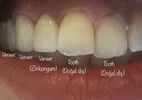

Zirkonyum uygulamalar

Porselen uygulamaları

Laminate veneer